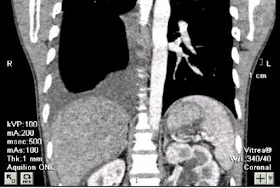

MRI  OF ABDOMEN DETECTED  ONE MASS  WELL BORDERED,  SIZE 4-3CM  INTRA PSOAS MUSCLE NEAR  LEFT LATERAL BORDER OF  LUMBAR SPINE L1  ( MRI 1).

MRI 2 : SAGITAL VIEW ,  MRI 3 :  T2 W.

RADIOLOGIST  SUSGESTED  A NEURO TUMOR